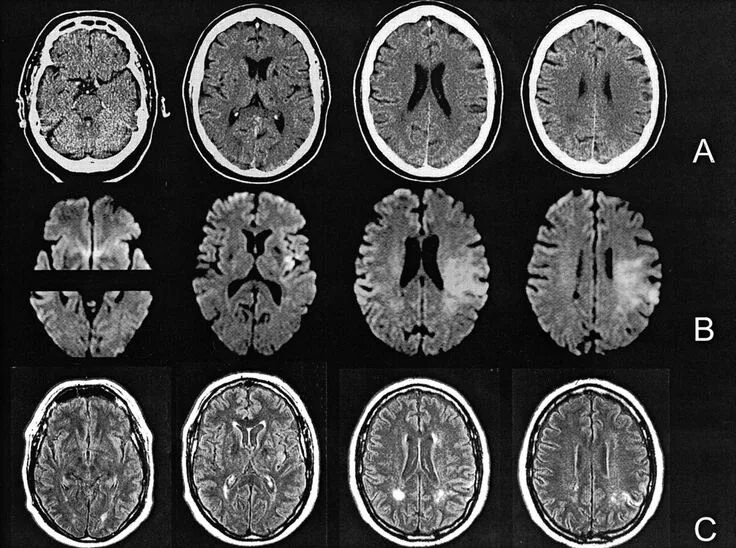

Мрт головного мозга и сосудов тула